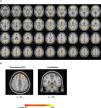

For the whole-brain analyses, relative to the CS-, CS+ evoked a widespread activation in the cortex (Fig. 3 and Table 1). These prominent regions include the cingulate gyrus, frontal medial regions, the frontal pole, and the cerebellum (I-IV).

With regards to the ROI analyses, the CS+ relative to the CS- evoked higher activation in the bilateral dlPFC and the right cerebellum (I-IV). The results of univariate analyses in the cerebellum across each run was illustrated in supplementary Table 1.